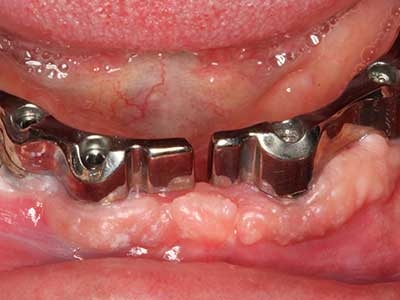

Indikation: Bone Splitting

Knochengewebe ist nicht nur rein mineralisch, sondern auch in wesentlichen Anteilen aus Kollagenfasern aufgebaut. Dies gewährleistet neben einer guten Druckfestigkeit eine gewisse Flexibilität, welche für die Durchführung von Augmentationen genutzt werden kann. Bei der klassischen Expansionsplastik im Sinne eines Bone Splittings wird der atrophierte Kieferkamm in seiner Längsachse gespalten und nach Erreichen einer ausreichenden Osteotomietiefe vorsichtig aufgedehnt (Abb. 13-16), idealerweise ohne den Kiefer wesentlich zu deperiostieren (Brugnami, Caiazzo et al. 2014, Stricker, Fleiner et al. 2014). Bewährt haben sich Schrauben- und Plattensysteme mit zunehmender Expansionsdistanz, um die beiden Knochenlamellen unterhalb der Bruchschwelle voneinander zu distanzieren. In der Regel werden Restknochenbreiten von mindestens 3-4 mm gefordert (Chiapasco, Zaniboni et al. 2006), um eine ausreichende Flexibilität und knöcherne Bedeckung der einzubringenden Implantate zu gewährleisten. Ggf. kann eine ein- oder beidseitige vertikale Entlastungsosteotomie die Flexibilität verbessern. Als Alternative zur klassischen Technik wurde eine Kombination mit weiteren augmentativen Techniken vor allem auf der bukkalen Seite beschrieben.

Mittels Piezosägen erfolgt die Anlage des Splittings besonders schonend und ohne wesentliche Dimensionsverluste, so dass sich keine signifikanten Unterschiede von Implantaten im gesplitteten Kiefer im Vergleich zum nicht defizitären Alveolarkamm gezeigt haben (Chiapasco, Zaniboni et al. 2006, Danza, Guidi et al. 2009). Gerade beim lokal begrenzten und tiefen Splitting ist jedoch stets auf eine ausreichende Wasserkühlung zu achten, um thermische Belastungen in den apikalen Osteotomiebereichen zu vermeiden.